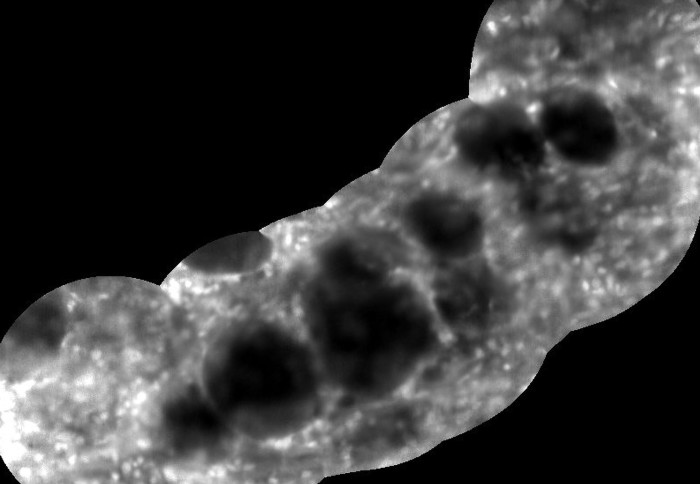

Image from microscope of invasive breast cancer cells

Microscope imaging of invasive breast cancer cells

When exploring spaces such as breast ducts in preliminary studies on cancer tissue, the instrument was able to pinpoint features smaller than a single cell. In live surgery, it could aid high-precision breast-conserving surgery by enabling surgeons to identify, extremely accurately and much more quickly than currently possible, suspicious tissue around tumours as well as cancerous cells just a hundredth of a millimetre across. It could also be used in the lungs, urinary tract, digestive system and brain in the future.